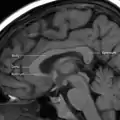

Задня частина мозолистого тіла — валок (лат. splenium); передня називається коліном (лат. genu); між ними знаходиться стовбур мозолистого тіла. Частина між тілом і валком звужена й називається перешийком (лат. isthmus). Ростральна платівка — частина мозолистого тіла, що знаходиться дозаду й донизу від найбільш передньої частини коліна мозолистого тіла, як показано на сагітальному зображенні мозку праворуч. Кінцеву її частину називають дзьобом (за схожість із пташиним дзьобом).

Мозолисте тіло на МРТ